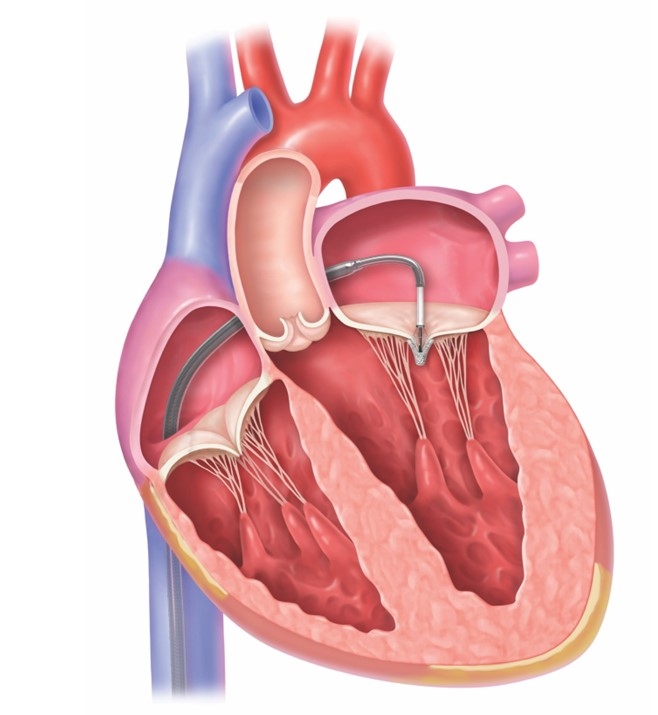

5. 経カテーテル心房中隔閉鎖術の実際

心房中隔閉鎖術はカテーテルを用いて左心房→右心房の順にディスクを広げ、心房中隔を閉鎖する治療です。将来的には、留置されたデバイスは内皮化されることが分かっています。

デバイスのサイズはいくつかあり、欠損孔の大きさによって選択されます。麻酔医による全身麻酔を行い、経食道心エコーによりデバイスを誘導します。治療時間は1〜2時間で、入院期間は約4日間です。

カテーテル治療の手順を下記にお示しします